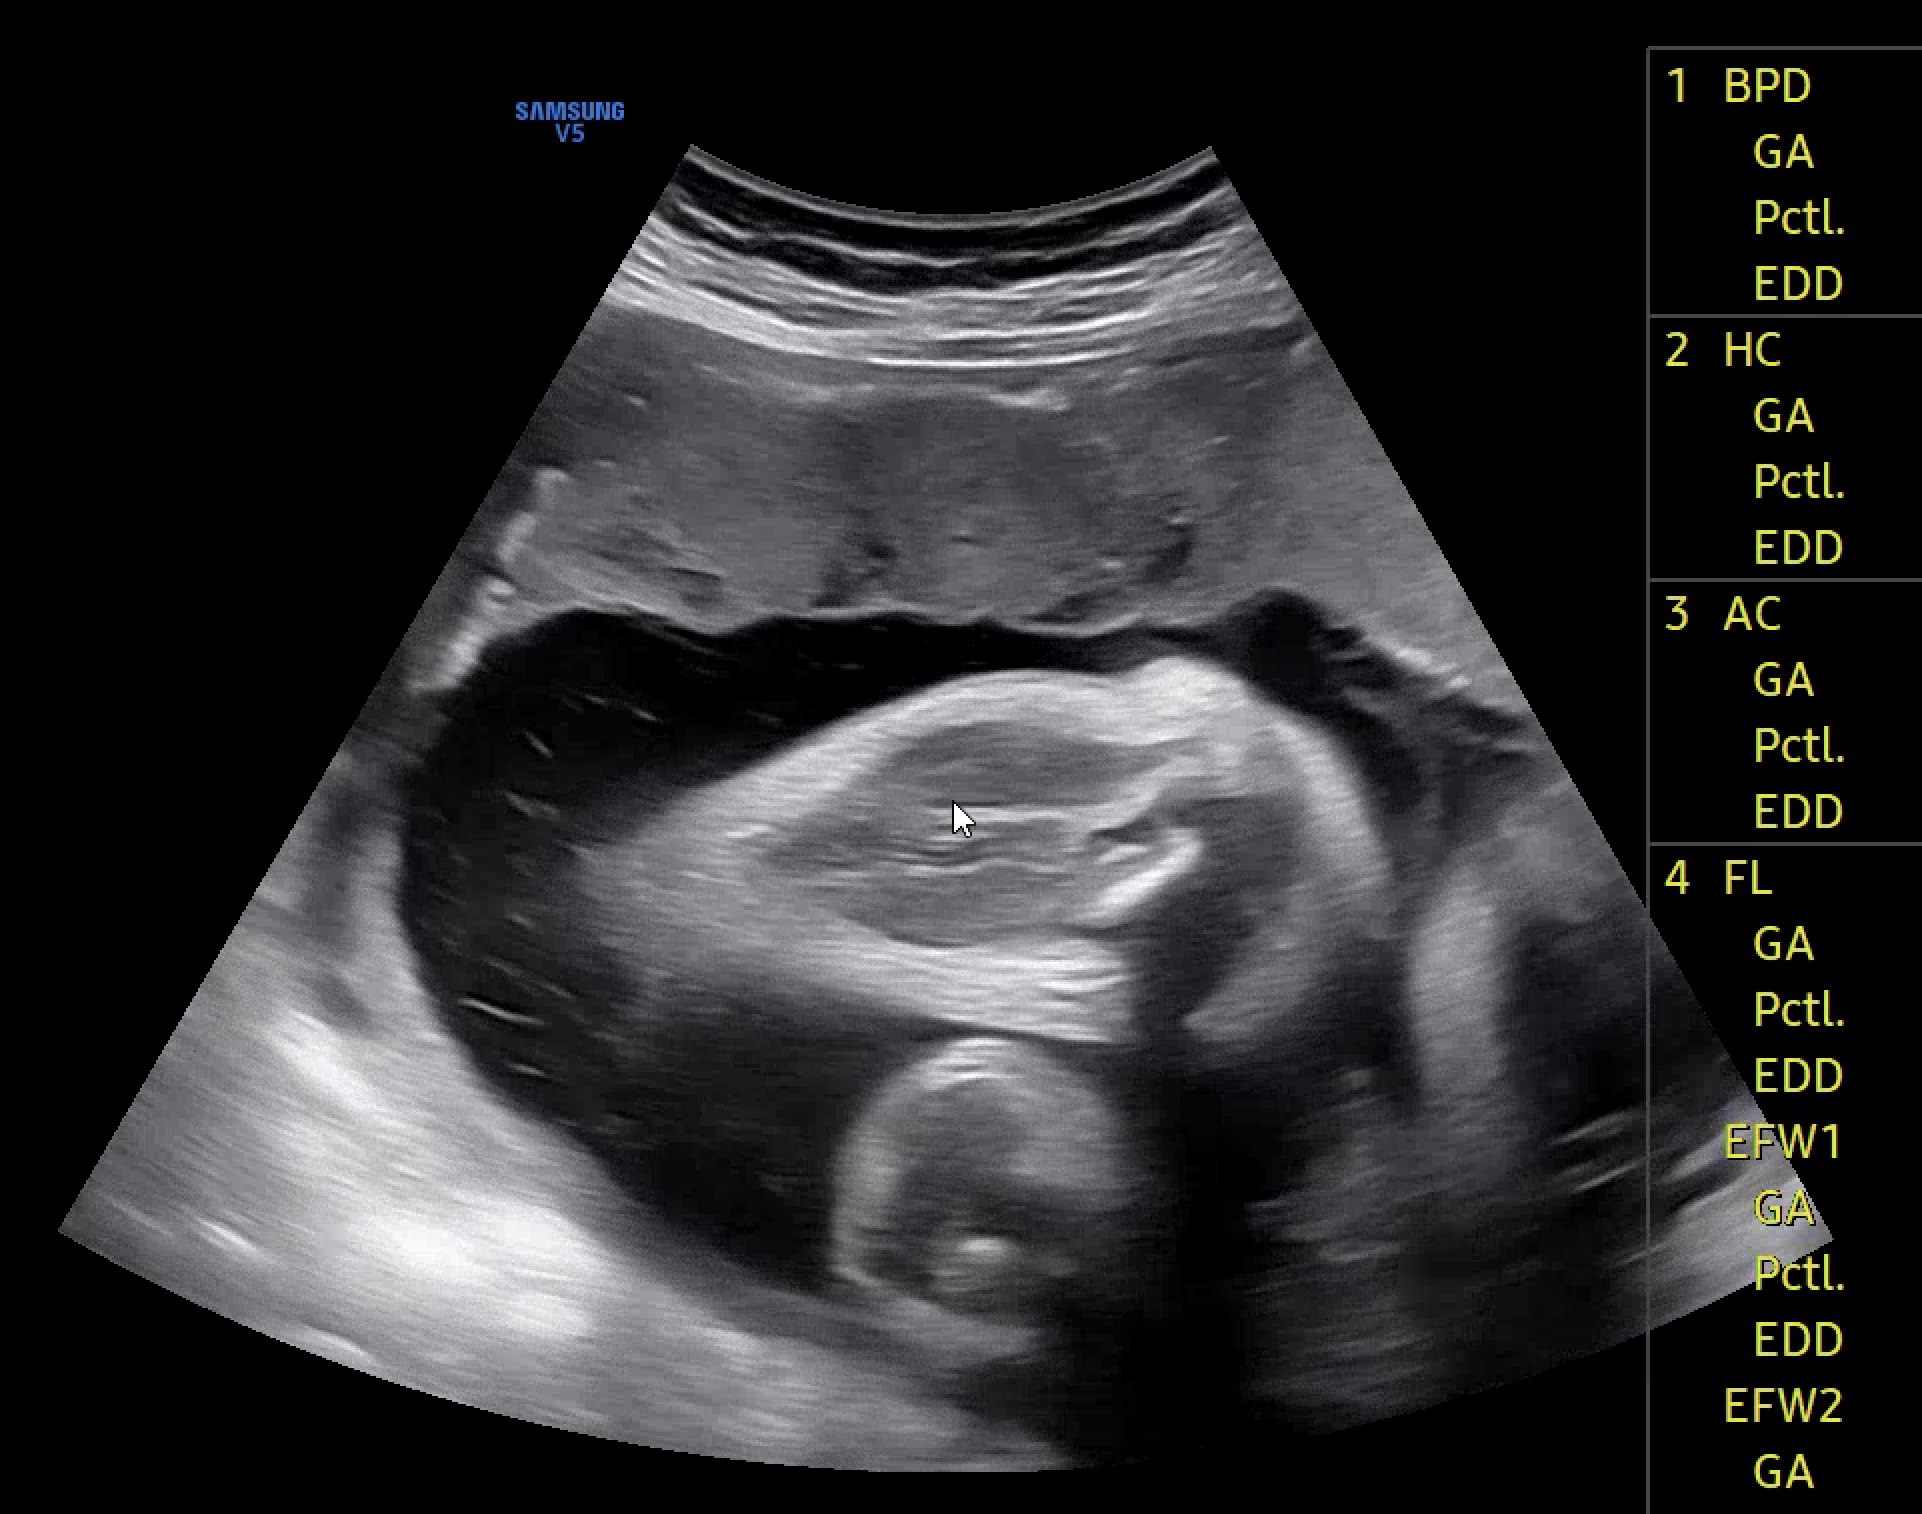

초기에는 초음파 영상이 입체인지 아닌지를 구분하는 것이 핵심 과제였다. 하지만 새로운 서비스 준비와 함께, 이미지 분류 기준을 보다 정교하게 세분화할 필요성이 생겼고, 이는 애초에 내가 지향했던 방향이기도 하다. 단순히 입체 여부를 판단하는 것을 넘어, 영상에 어떤 성장 지표가 (예: AC, BPD, FL) 포함되어 있는지를 구체적으로 분류하고 싶었다. 수많은 시행착오 끝에 구조가 또렷이 보이는 이미지는 ac, bpd, fl 등 긍정 클래스로, 구조 식별이 어려운 이미지는 부정 클래스로 나눠 학습시켰다.

여기서 핵심 기준은 영상 내 십자가 모양의 마커와 (marker) 어노테이션의 (annotation) 존재 여부다.

- 마커와 어노테이션 모두 있는 경우 → 긍정 클래스로 분류 (ac, bpd, fl 등)

- 마커는 없지만 어노테이션이 있는 경우 → no_xxx 클래스로 분류

- 마커도 없고 어노테이션도 없는 경우 → na_xxx 클래스로 분류